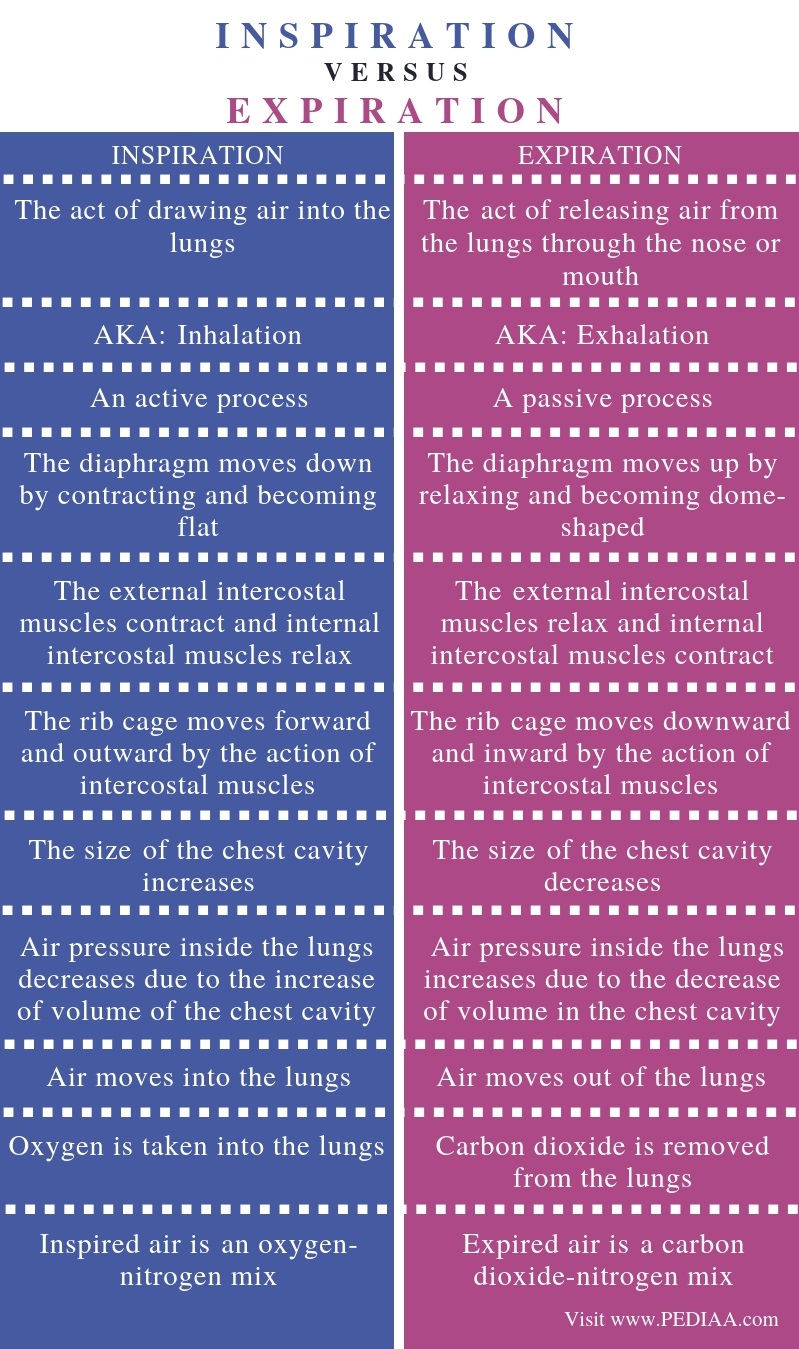

Normal Difference Between Chest Inspiration And Expiration

Normal Difference Between Chest Inspiration And Expiration

More picture related to Normal Difference Between Chest Inspiration And Expiration

Mechanism Of Breathing As Anatomical Process Explanation Outline

Mechanism Of Breathing As Anatomical Process Explanation Outline

Normal Difference Between Chest Inspiration And Expiration - 2025 DIY